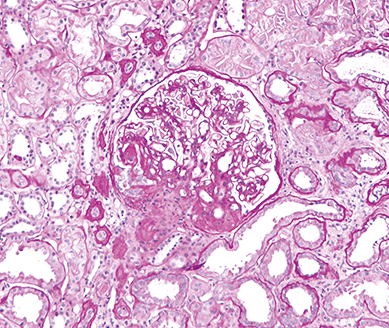

Dickkopf 3 ist ein neuer Biomarker zur Diagnose einer progredienten tubulointerstitiellen Fibrose. DKK3 wird von gestressten Tubuluszellen in den Urin freigesetzt. Der neue Biomarker liefert eine Aussage über das Fortschreiten einer tubulointerstitiellen Fibrose und ist ein unabhängiger Indikator für den Nierenfunktionsverlust. Der neu entwickelte DKK3-ELISA ermöglicht die Erkennung einer chronisch fortschreitenden Nierenvernarbung mit einer einfachen Bestimmung von DKK3 im Urin. Sie eignet sich deshalb hervorragend als Zusatzinformation zur GFR, einem etablierten Parameter der Nierenfunktion, um den individuellen Verlauf einer chronischen Nierenschädigung besser abzuschätzen. Bei einem negativen Ergebnis (DKK3 < 200 pg/mg Kreatinin) liegt mit hoher Wahrscheinlichkeit keine Progression der chronischen Nierenschädigung vor. Im Falle eines positiven Ergebnisses (DKK3 > 200 pg/mg Kreatinin) liegt mit hoher Wahrscheinlichkeit eine progrediente chronische Nierenschädigung vor. Die Interpretation der DKK3-Ergebnisse sollte immer in Verbindung mit der GFR erfolgen.

• DKK3 wird von gestressten Tubuluszellen in den Urin freigesetzt